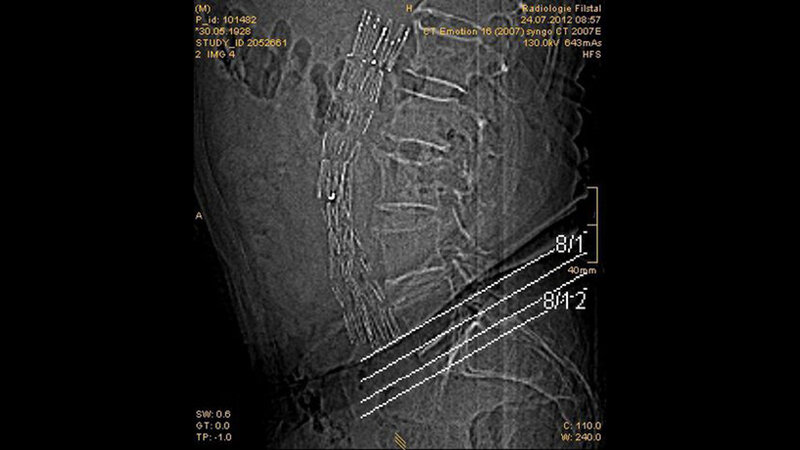

Schnittbilddiagnostik der Wirbelsäule (7.17)

Die Aorta als das größte arterielle Gefäß des Körpers kann bei Schnittbilduntersuchungen der Brust- und der Lendenwirbelsäule mit beurteilt werden.

Bestimmte MR-Sequenzen können bei der Nitinol- und Platinum-Iridium-Stent-Darstellung großer Gefäße mit der CT vergleichbare Ergebnisse liefern. Ultraschall, CTA und MRT sind sensitive Methoden in der Detektion von pathologischen Gefäßveränderungen. CT und MRT sind zuverlässige Methoden zur Erfassung aller relevanten Informationen in der Kontrolle von Gefäßprothesen.